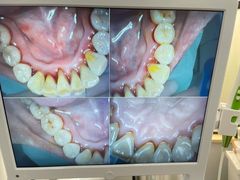

• 牙博士口腔品牌连锁(杨浦店)

• -牙博士口腔品牌连锁(杨浦店)

囍 | 22-08-11